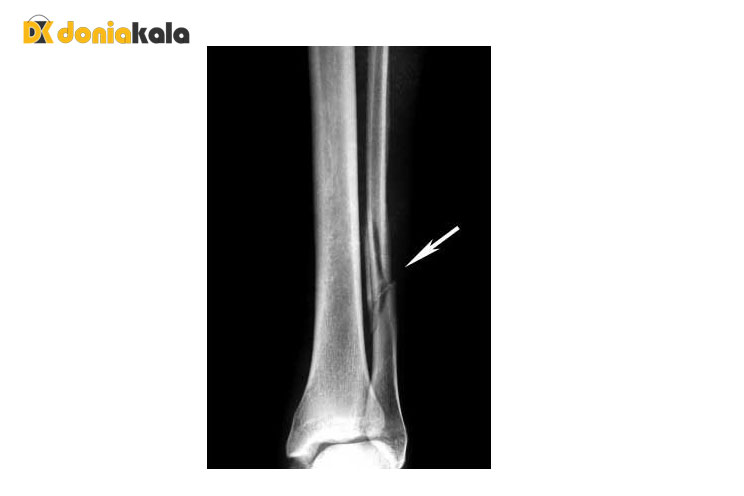

شکستگیهای شفت فیبولا : شکستگیهایی هستند که در وسط استخوان نازک نی مشاهده میشوند.